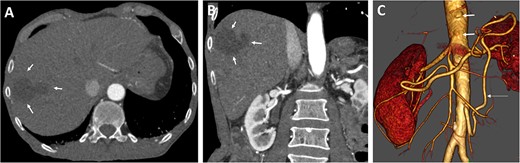

Preoperative axial (A) and coronal (B) CT angiographic images demonstrate hypoenhancement of all of the hepatic parenchyma and hypodense, hepatic lesion measuring 48 × 47 × 34 mm in the segment V and VI (arrows). (C) 3D reconstructed CT angiography shows occlusion of the celiac and superior mesenteric arteries (thick arrows) and hypertrophy of the inferior mesenteric artery and artery of Drummond (thin arrow).